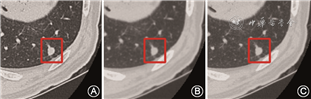

所有胸部CT平扫数据均来自多排螺旋CT(GE Discovery CT,美国GE公司)。检查时患者采取仰卧位,于吸气末行胸部CT扫描,扫描参数为120 kV,层厚1 cm,图像矩阵512×512,重建层厚1.25 mm。每例患者的胸部CT都包括肺重建、纵隔重建、骨重建三种重建算法的图像(图1)。